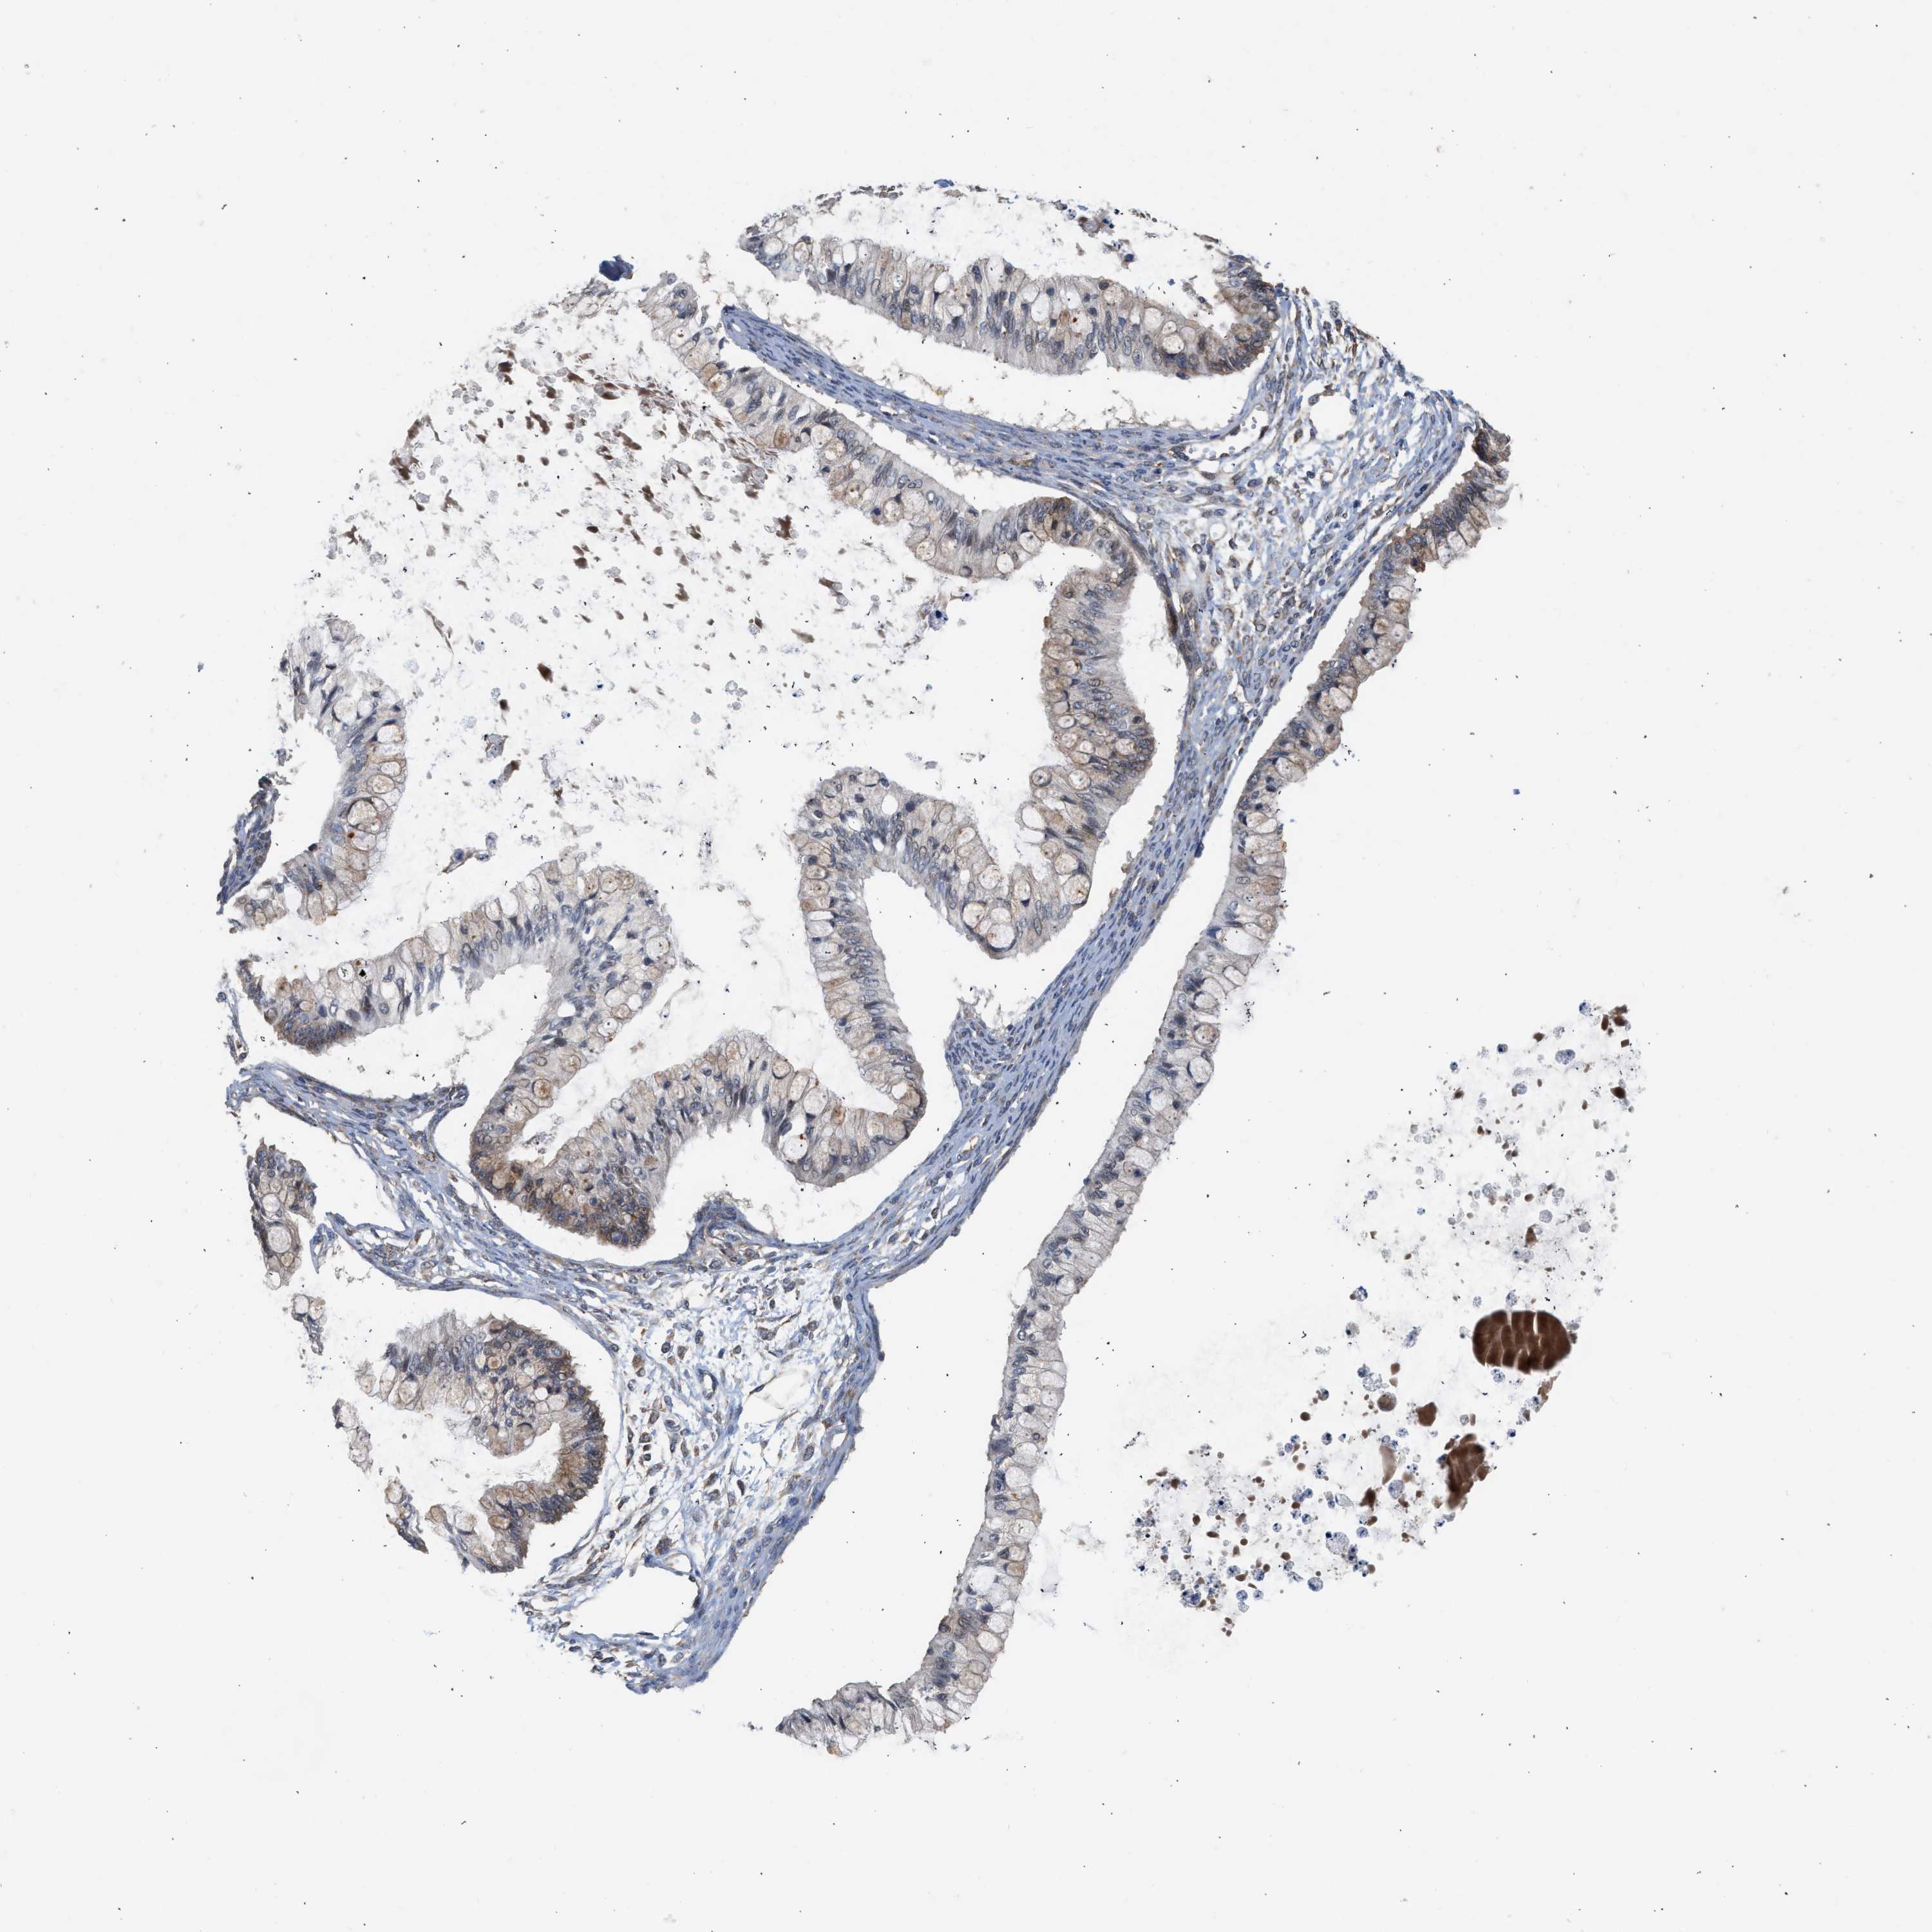

OVARIAN CANCER - Protein expressioni

A mouse-over function shows sample information and annotation data. Click on an image to view it in a full screen mode. Samples can be filtered based on level of antibody staining by selecting one or several of the following categories: high, medium, low and not detected. The assay and annotation is described here.

Note that samples used for immunohistochemistry by the Human Protein Atlas do not correspond to samples in the TCGA dataset.

Antibody stainingi

Antibody staining in the annotated cell types in the current human tissue is reported as not detected, low, medium, or high, based on conventional immunohistochemistry profiling in selected tissues. This score is based on the combination of the staining intensity and fraction of stained cells.

Each image is clickable and will lead to virtual microscopy that enables deeper exploration of all samples and also displays staining intensity scores, fraction scores and subcellular localization as well as patient and tissue information for each sample.

Antibody HPA023202

Antibody CAB017030

Cystadenocarcinoma, serous, NOS

Carcinoma, endometroid

Cystadenocarcinoma, mucinous, NOS

Carcinoma, NOS